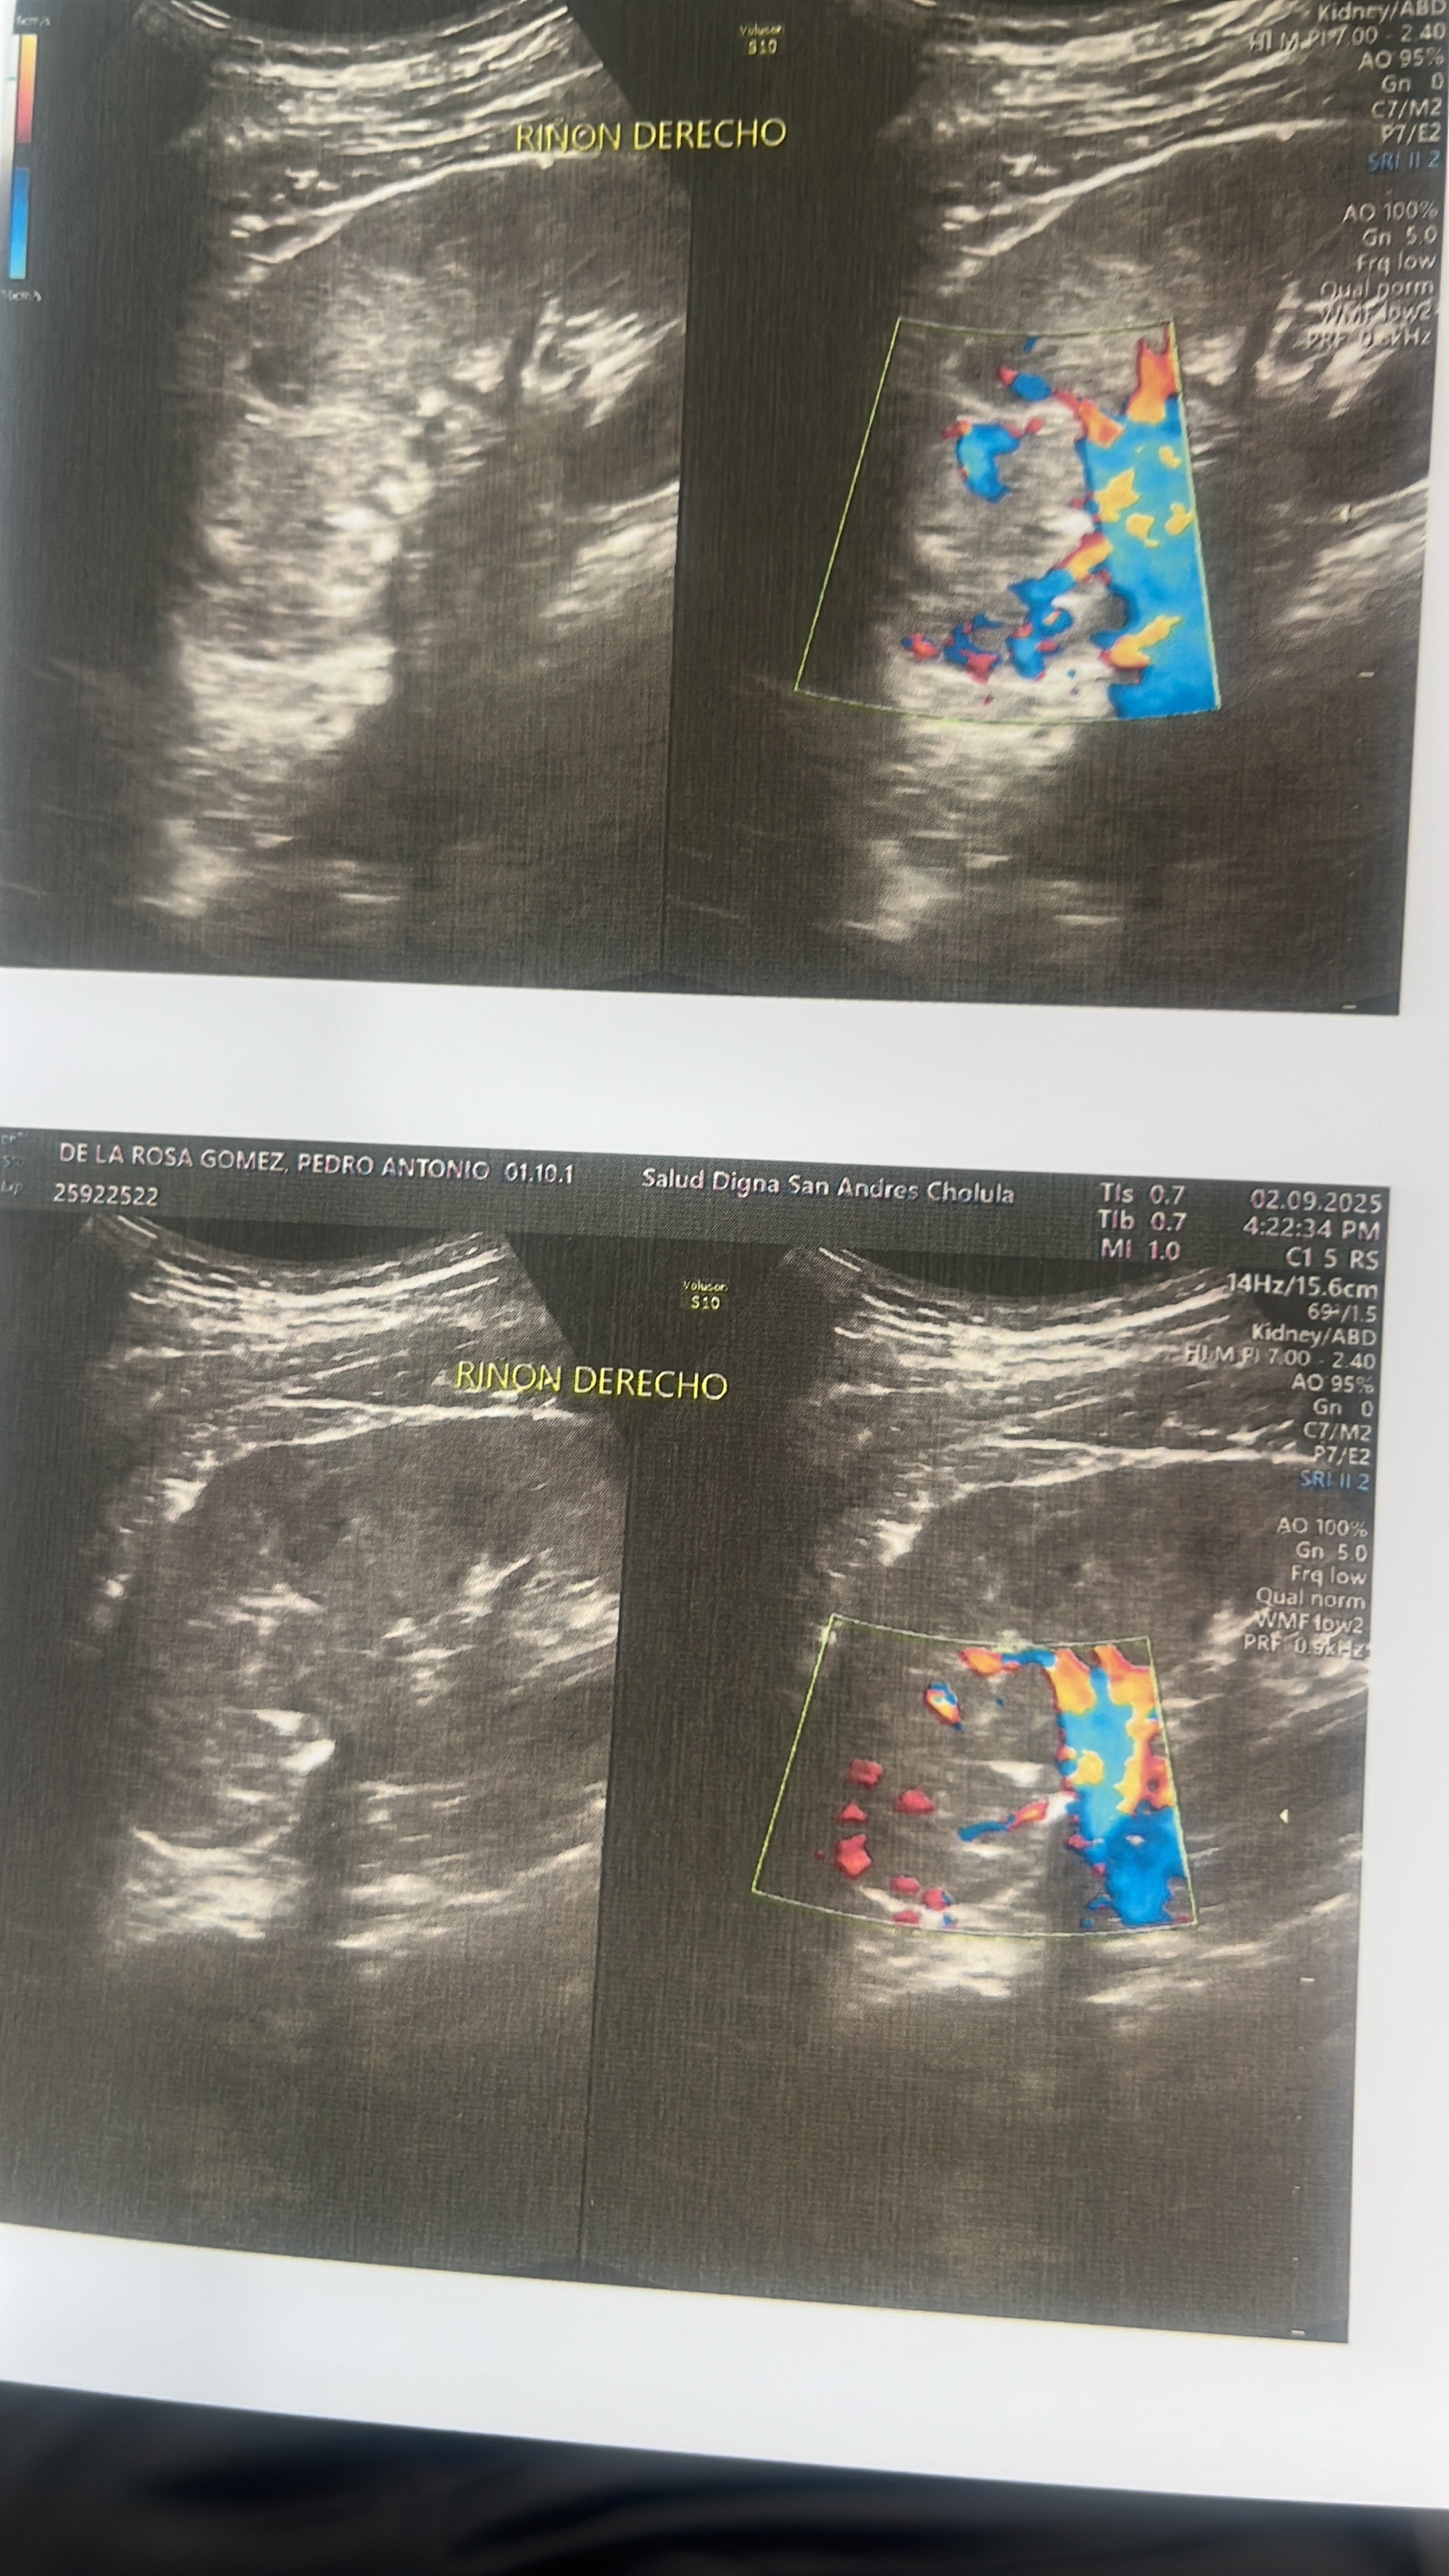

Hola, me llamo Pedro tengo 33 años, muchos me conocen como Peter ! A lo largo de mi vida he ayudado a niños con leucemia, de escasos recursos y personas en vulnerabilidad. Hoy la voluntad de Dios me pone una prueba muy difícil en el camino, superar un tumor con el 96% de probabilidad que sea maligno, se encuentra en mi riñón derecho, por lo cual van a extraerlo al igual que mi riñón... es preocupante por que al extraerlo el patólogo determinará mi situación, por la urgencia de la cirugía tiene que ser en hospital privado, por eso pido su apoyo para llegar a personas de buen corazón que deseen unirse y pronto puedan operarme, les seré sincero vendí mi auto y entre mi familia ya casi llegamos a la meta nos falta un granito más y lo que venga después.. Tengo ganas de seguir ayudando a muchos pequeños Dios los bendiga y si gustan visitar mi Facebook me encuentran como Peter de la Rosa Gomz ahí conocerán más de mi historia. Bendiciones